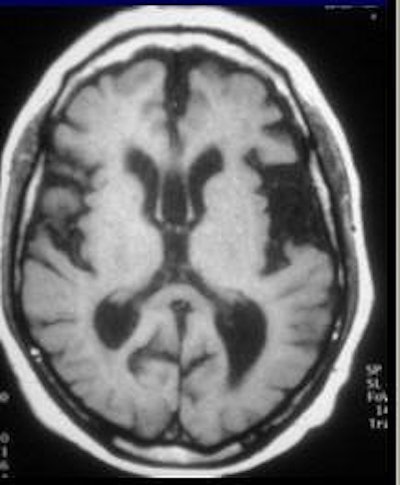

![]() |

| The advantage of using MRI to track NPH is that imaging can be done in any plane. MR is also more sensitive to interstitial, transependymal flow of cerebrospinal fluid, and hyperdynamic CSF flow seen with shunt-responsive NPH, as seen above (Neurosurgery Clinics of North America, October 2001, Vol. 12:4, pp. 661-684, viii). Image courtesy of Dr. William Bradley Jr., Ph.D. |